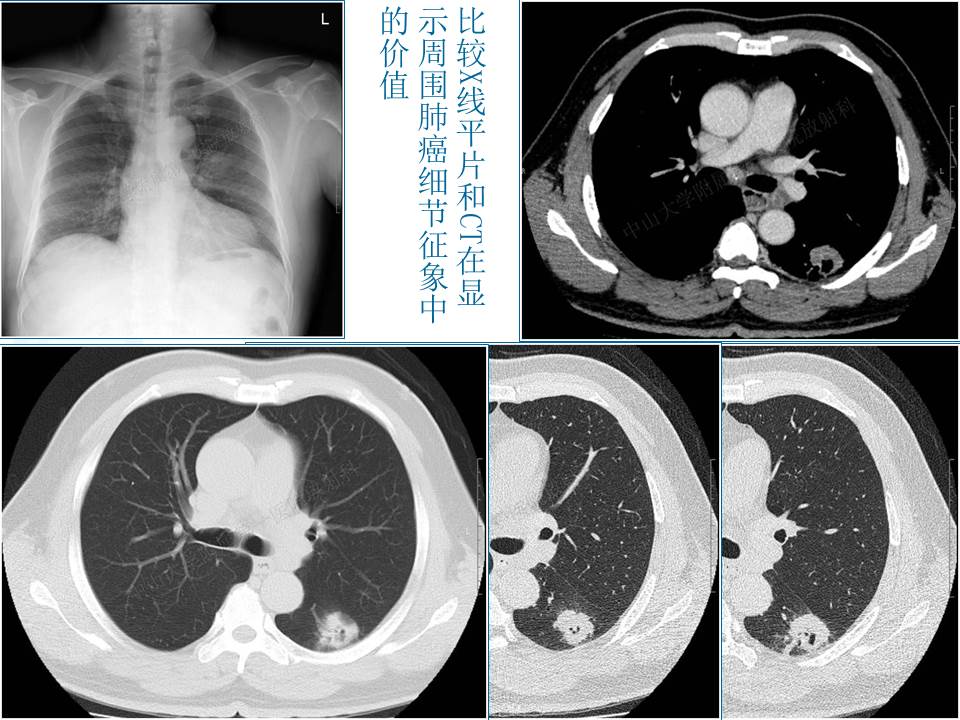

支气管肺癌的影像学诊断